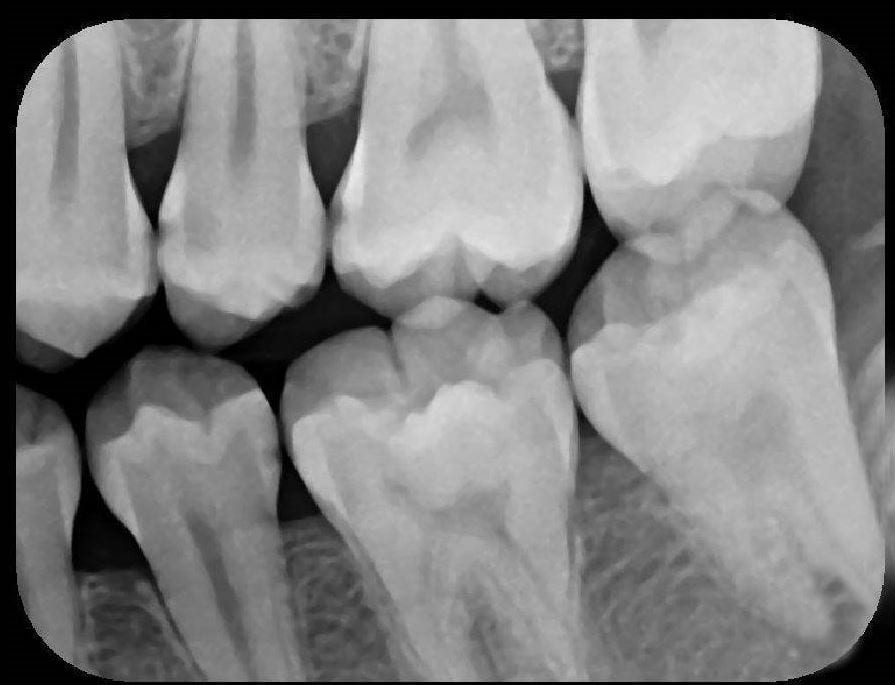

X-Ray 4: How many caries are present?

(Required)

X-Ray 4: How many PAP's are present?